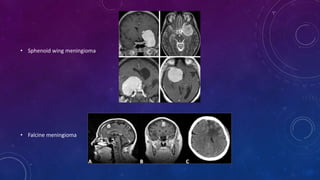

• Sphenoid wingmeningioma • Falcine meningioma

• Sphenoid wing meningioma

• Falcine meningioma

LOCATION • The anatomiclocation of a meningioma influences its rate of recurrence. Tumors that are more difficult to remove totally, such as meningiomas of the sphenoid wing, recur more often. Meningiomas that invade a dural sinus, such as parasagittal meningiomas, have a high rate of recurrence. The recurrence rates of meningiomas differ from one series to another; the highest recurrence rates (>20%) are found in patients with sphenoid wing meningiomas, followed by those with parasagittal meningiomas (8% to 24%). The recurrence rate for convexity and suprasellar meningiomas is 5% to 10%.